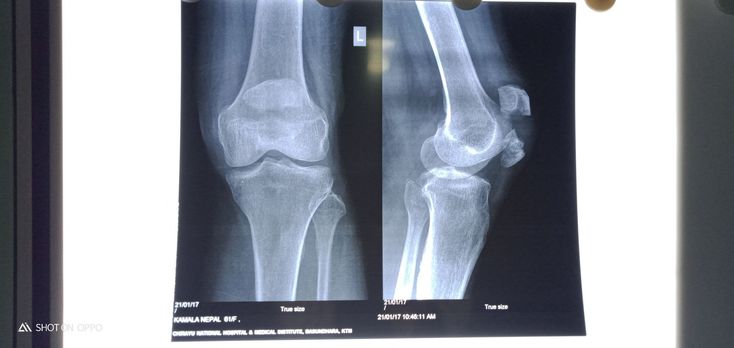

What is your diagnosis

Multiple fracture of patella